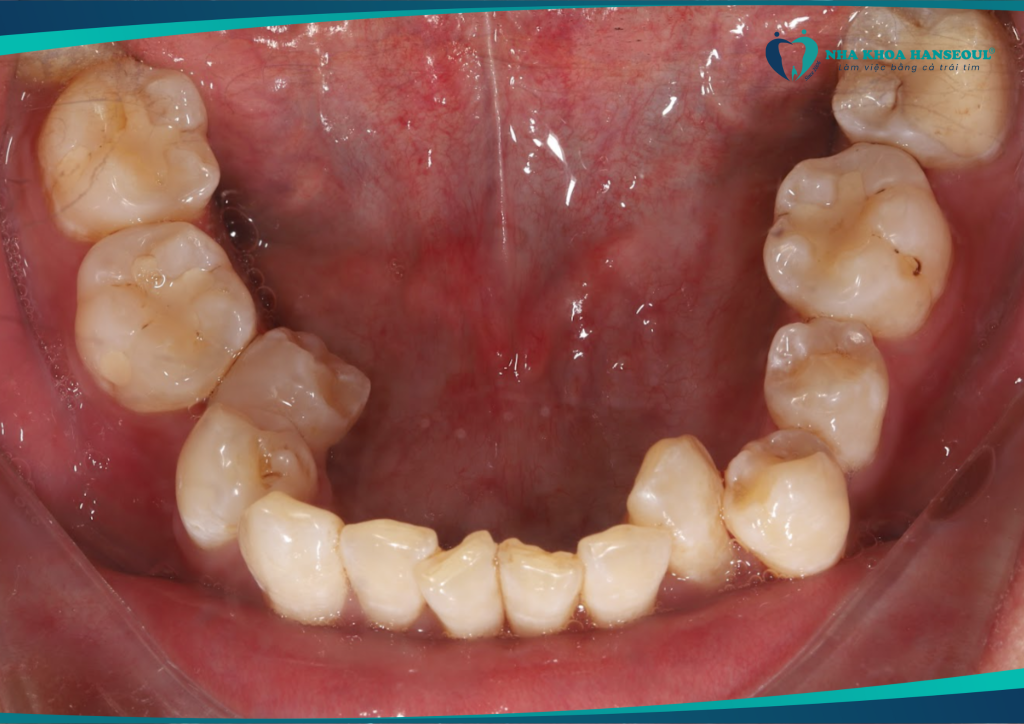

1 Tình trạng răng trước điều trị: Khớp cắn ngược hạng III móm, răng khôn sâu

Anh Trường gặp phải tình trạng khớp cắn ngược hạng III móm. Đây là một dạng sai khớp cắn khiến hàm dưới đưa ra trước. Ảnh hưởng đến cả chức năng ăn nhai lẫn thẩm mỹ khuôn mặt. Ngoài ra, anh còn gặp tình trạng răng khôn sâu, thường xuyên đau nhức. Ảnh hưởng lớn đến sinh hoạt hằng ngày.